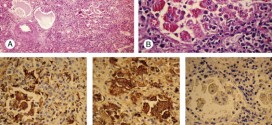

MELANOMA DE RIÑON

El melanoma de riñon. Tumor maligno en general y especialmente el formado por células epiteliales, se presenta en el parénquima del riñón, es la forma más usual de cáncer y se origina en la proliferación de células epiteliales de los túbulos renales. Durante los primeros años de vida de una persona, las células normales se dividen más rápidamente para permitir …